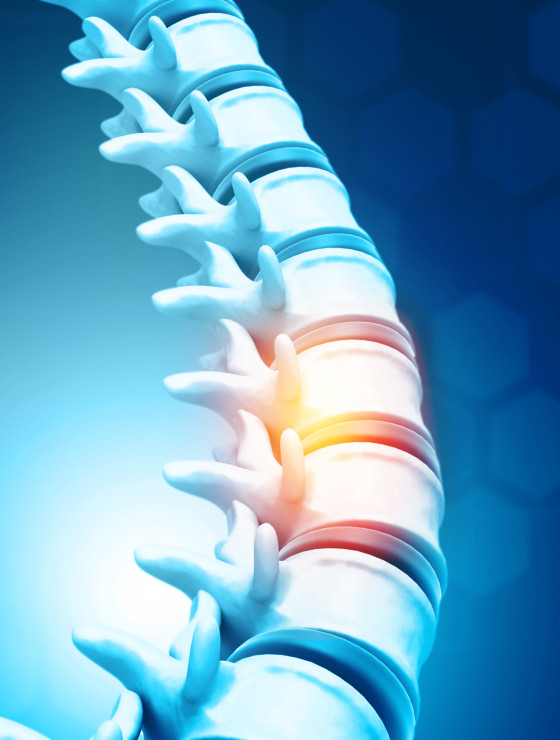

Inovação e tratamento da hérnia de disco

Cirurgias na coluna são seguras e previsíveis. Ao longo das últimas décadas observou-se refinamento das técnicas operatórias e dos equipamentos de projeção de imagens, como microscópios e vídeo-endoscópios. Hoje é possível “navegar” em cirurgias guiadas por tomografia tridimensional, além de monitorar a atividade neurológica do paciente em tempo real.